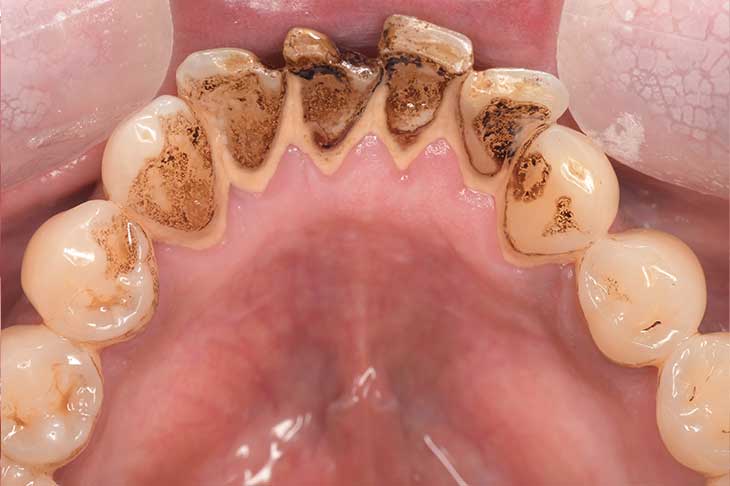

歯の表面についたステインがわかりやすい口の中の写真

※40代・男性:喫煙習慣ありの患者さま